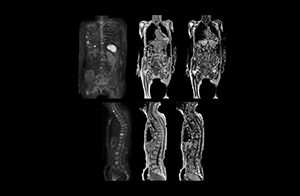

“When we limited the scan coverage to the area from neck to femur, we could fit more clinical information in approximately the same scan time. So, we added coronal mDIXON, sagittal T1-weighted, and sagittal STIR sequences to our examination, instead of performing only axial DWIBS and coronal single-shot TSE scans.” The single shot T2-weighted TSE images are used for morphology and compared to DWIBS images to identify T2 shine-through. Sagittal STIR images are used in patients with inflammation or bone metastasis.

“Switching to coronal DWIBS – rather than axial – further shortens scan time,” says Mr. Naka. “Important is that a dS SENSE factor of 5 shortens exam time while high image quality can be maintained, thanks to Ingenia’s dStream architecture.” He adds that the coronal orientation also avoids artifacts that are specific to combining axial images.